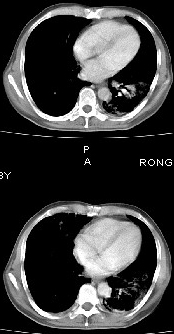

男68岁,反复发热、咳嗽,咯痰1月,曾有咯血史,双肺闻及呼吸音增粗。

左肺上叶尖后段及下叶多发实变阴影,内见支气管充气征,段以上支气管尚通畅,肺门区未见软组织肿块影,结合病人有反复发热病史,首先考虑感染性病变(干酪性肺炎不能排除),建议抗炎治疗后复查或结合纤支镜检查。

左肺上叶尖段及下叶干酪性肺炎可能性大,建议结合临床相关检查.右肺中叶炎症.建议治疗后复查.

该患者在25天前外圆平片见右肺中上肺野大片状影,(治疗不祥,在反复问病史后患者告诉;近一月住在新房内,搞装修),我认为首先考虑是感染,而且过敏性肺炎可能性大。